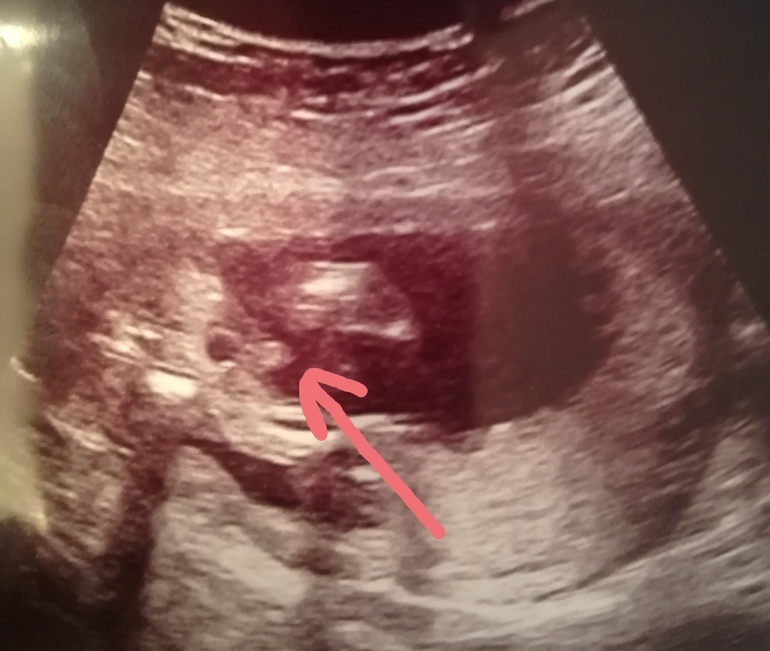

В итоге, узистка сделала фото, со словами "ну вот как то так. Тут 2 варианта. Либо это у вашего богатыря уж очень большое мужское начало, либо закрутил пуповину между ножек!" ставит мальчика, но под вопросом.

Я вижу большой писюн, папа видит пуповину. 😂🙈 Кто что скажет? 😂

Как нормальный узист в 17 нед не увидит писюна? Ппц. Похоже на парня, но чет я не наблюдаю мошонки. Но я и не узист!

В16 недель только плохой узист не отличит писюн от пуповины.